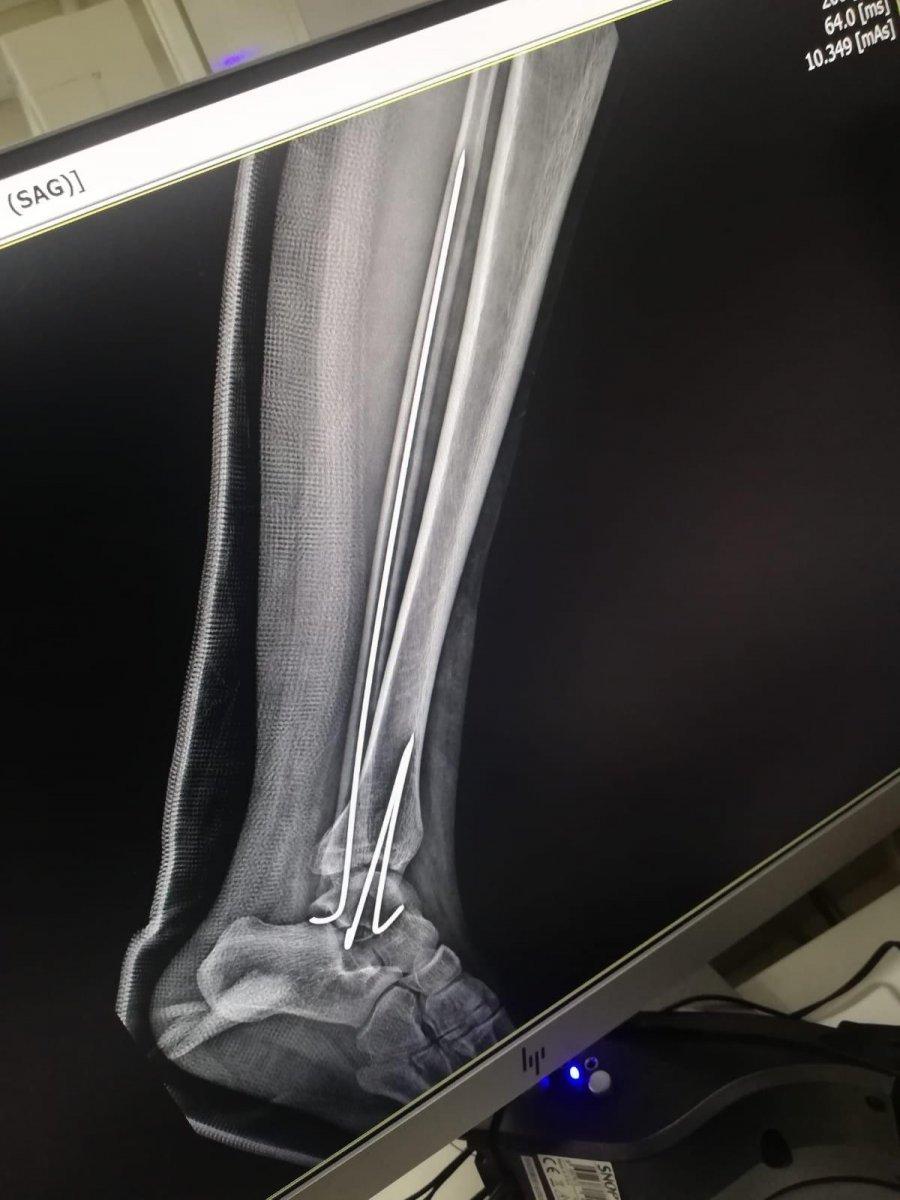

Burada ilk tedavisi yapılan küçük kızın sol bacak ve kolu ile kalça ve kuyruk kemiğinin kırıldığı tespit edilmiş ve Bezmialem Vakıf Üniversitesi Hastanesi'ne kaldırılarak tedavi altına alınmıştı. 9 ay geçen olayın sonrasında Elif Koşucu’nun düşmeye bağlı olarak topallayarak yürüyebildiği, sol koluna platin takıldığı ve sol ayak bilekliğine de yürüyebilmesi için özel bir apart takıldığı öğrenildi.